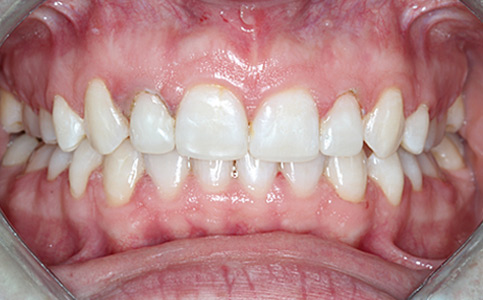

Dzięki koronom pełnoceramicznym w szczęce i żuchwie oraz uzupełnieniu braków zębowych implantami, pacjentka może znów się szeroko i pięknie uśmiechać.